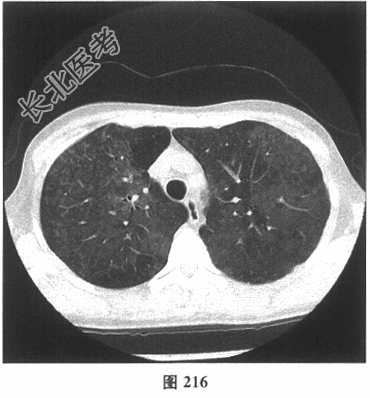

- [材料题] 患者女性,职员,43岁,以"反复咳嗽2个月余,咳痰、活动后气喘2周"就诊。体检:双肺未闻及干湿性啰音。既往无吸烟史。肺部CT见图216~图219。

- 多项选择题2.[提示]患者发病前3个月曾装修过房屋。目前考虑患者最可能的诊断为( )